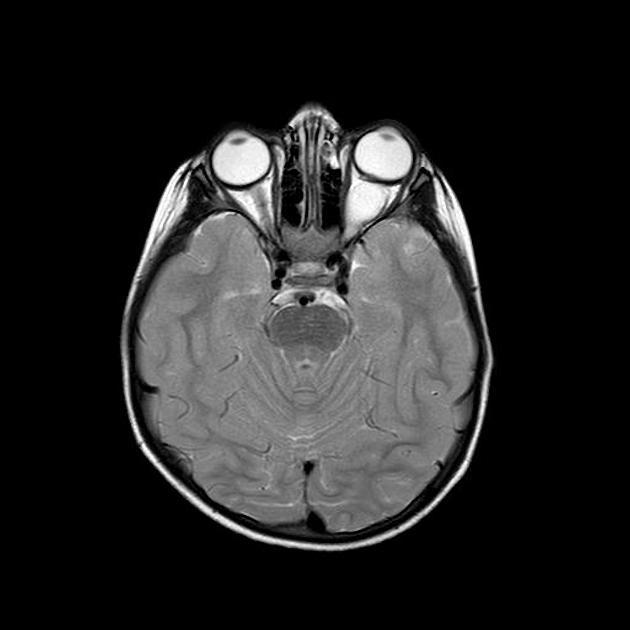

案例一

基本病史:6 岁女孩,既往体健,近期左眼视力明显下降,行颅脑 MRI 检查结果如下。

图 1 MRI 检查轴位 T2WI 序列显示鞍区及鞍上区见长 T2 异常信号实性肿块,沿视神经走行